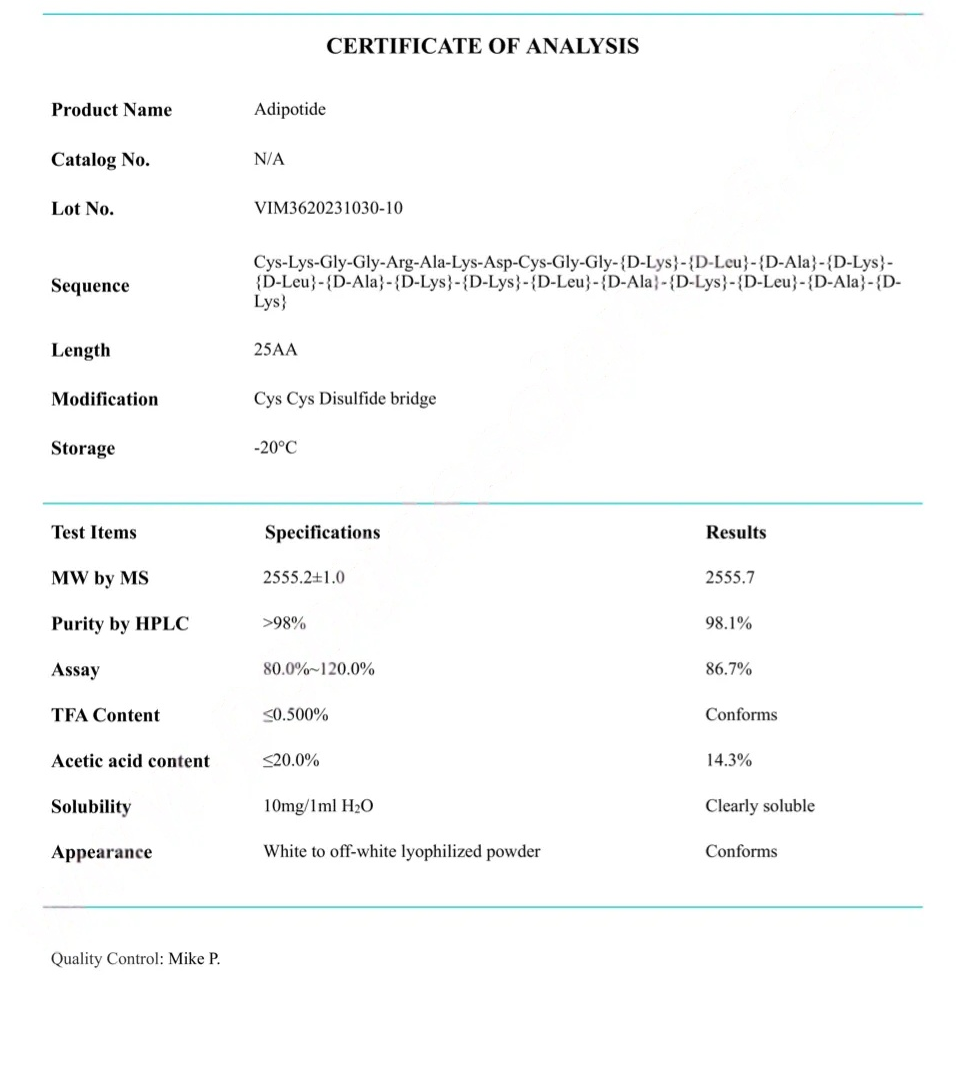

Adipotide (FTPP) COA CERTIFICATE

HPLC Adipotide (FTPP) Certificate

MS Adipotide (FTPP) Certificate